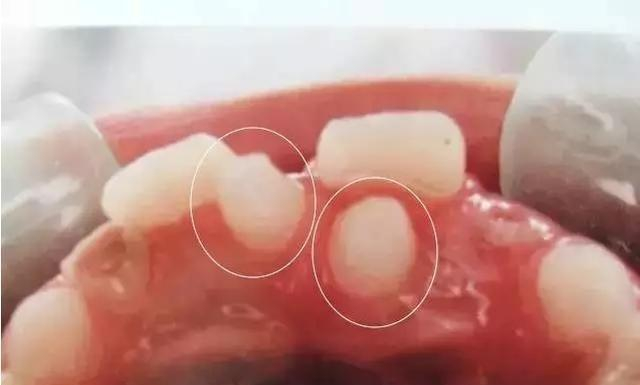

多生牙又称额外牙,是正常牙列以外的多余牙齿,是多于正常牙数以外的发育异常的牙齿。在形态上,其多为锥形牙或者过小牙,也可与正常牙齿形态相似。在数量上,可分为单发或者多发。在位置上,可分为正中、前磨牙区、磨牙区等,其中上颌前牙区最为常见。在空间上,可萌出在口腔,一般口内检查可见;也可埋伏阻生,只能通过X线检查发现。

多生牙往往没有临床症状,多在拍片时偶然发现。但其危害不容忽视,可影响恒牙的发育,可引起恒牙的迟萌或者阻生,恒牙牙根形态发育异常,出现牙间隙、牙齿扭转或者移位。多生牙可能横着、倒着、斜着埋伏在颌骨里占据正常牙齿的位置,从而影响恒牙的萌出。甚至,久而久之,多生牙阻挡恒牙牙根正常生长方向,导致恒牙牙根弯曲。此外,多生牙也可以在乳牙脱落前后萌出,临床上我们看见形态不正常的牙齿或者牙尖。萌出的多生牙占据了正常恒牙在牙列中的位置,造成牙列不齐。

2 牙齿移位

3 牙间隙大